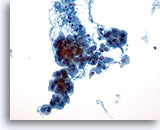

Positivo per carcinoma papillare

I campioni appartenenti a questa categoria sono quelli in cui all’istologia viene individuata una patologia maligna nel 100% dei casi. Il carcinoma papillare costituisce il tumore maligno della tiroide più diffuso e presenta caratteristiche nucleari specifiche facilmente identificabili nei campioni citologici. Altre patologie maligne diagnosticabili con un elevato grado di accuratezza grazie alla citologia sono: carcinomi midollari, linfomi e carcinomi metastatici. Nei campioni ThinPrep il carcinoma papillare è è caratterizzato da lembi e aggregati papillari di cellule affollate con nuclei ingranditi e a stampo, cromatina “polverosa”, membrane nucleari irregolari messe in evidenza da solchi nucleari e inclusioni citoplasmatiche intranucleari e nucleoli piccoli ma prominenti e spesso eosinofili. [7] Al contrario, il carcinoma midollare è caratterizzato da cellule plasmocitoidi monomorfe isolate con un rapporto N/C elevato, nuclei eccentrici e cromatina vistosamente granulare con o senza nucleoli prominenti. Il citoplasma è granulare con granuli piccoli e appena visibili. In alcuni casi, le cellule appaiono affusolate, ma presentano le stesse caratteristiche nucleari. I linfomi e i carcinomi metastatici della tiroide sono molto meno diffusi. Le caratteristiche citologiche dipendono, nell’ordine, dall’istotipo e dal sito di origine.